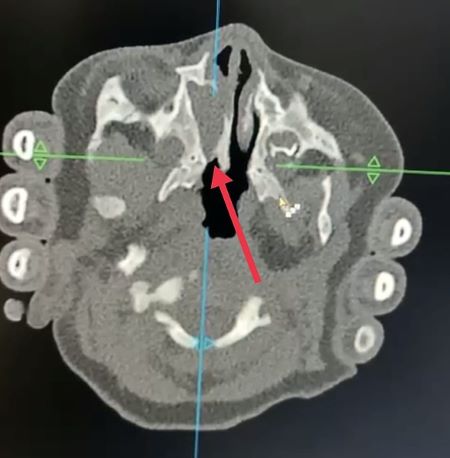

Взят мазок на флору и чувствительность (в последующем - патогенной микрофлоры не обнаружено). Принято решение о дополнительном методе исследования: КТ носоглотки (произведено в нашей клинике). Зачастую детям проводят данное исследование под наркозом. В данном случае (по договорённости с мамой, в случае, если вдруг не получится, то в стационаре проведут под наркозом) обошлось без наркоза. На компьютерной томограмме полости носа и околоносовых пазух определяется сужение задней части носовой полости справа до 2,8 мм, слева до 1 мм с частичной обструкцией костной тканью.

После проведённых исследований и консультаций был установлен диагноз: изолированная врожденная правосторонняя костно-мембранозная частичная атрезия хоан.